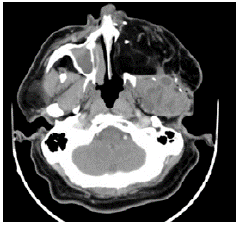

Eleven years after the initial surgery, and after 3 surgeries, a new local relapse was discovered. On physical examination, the patient was found in good condition, with left facial palsy and mass in left masticator space with extension to hard and soft palate, in addition to left submandibular ganglion conglomerate. Contrasted CT showed a mass that involved the left masticator space, lobed, of heterogeneous density with extension towards the skull and average cranial fossa of 36.7x53.6x42mm in anteroposterior section (Figures 3 and 4); biopsy and histopathological study confirmed ameloblastoma.

Follicular cystic ameloblastoma and plexi-form ameloblastoma were identified in all the pathologies analyzed since the initial biopsy and in the different surgical specimens (Figures 3 and 4), both from the local resections and the scalp lesion. No genetic profile of BRAFV600E mutation was performed, since it was not requested during the period when the samples were processed and it is not a routine test performed in the institution.